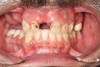

A 71-year-old female patient presented with a maxillary complete denture and a failing mandibular dentition. The patient wore an ill-fitting mandibular acrylic removeable partial denture to supplement her periodontally compromised mandibular teeth. She expressed a desire to improve the esthetics and function of her teeth and to replace her removeable partial denture with a fixed prosthesis. (Case 4 is depicted in Figure 43 through Figure 52.)

An initial appointment included a complete oral examination as well as a panoramic x-ray, CBCT scan, and intraoral surface scans of her maxilla and mandible. A comprehensive treatment plan included extraction of her mandibular teeth with immediate implant placement and insertion of a mandibular full-arch immediate fixed provisional restoration followed by a final mandibular full-arch fixed zirconia restoration.

The treatment began by addressing the patient's immediate concern, which was her mandibular situation. Her mandibular teeth were extracted, and immediate implants were placed and immediately provisionalized using a screw-retained PMMA provisional, which sat on multi-unit abutments.